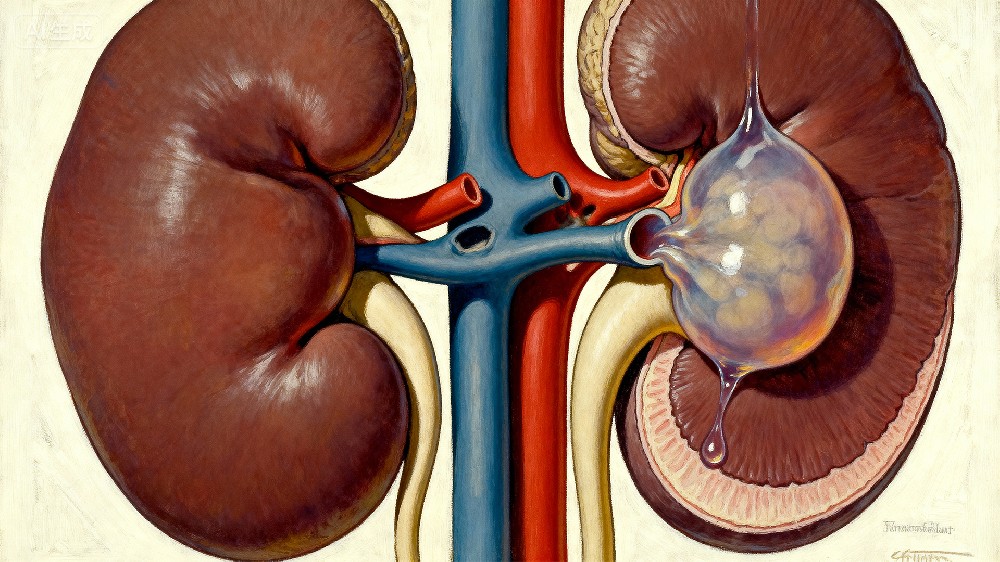

肾结石是一种常见的泌尿系统疾病,表现为腰腹部绞痛、血尿和排尿困难,严重时可导致尿路梗阻、感染和肾功能损害;其发生与饮食、饮水量、代谢因素及环境相关,但遗传易感性在结石形成中同样起重要作用,因此肾结石易感基因检测有助于提前识别高危人群,促进早预防和个体化管理。

与肾结石相关的代表性基因包括SLC34A1和SLC34A3(影响肾小管磷酸盐转运)、SLC22A12和ABCG2(尿酸排泄相关基因,变异可增加尿酸结石风险)、CLDN14(影响肾小管钙重吸收)、CASR(钙感受器基因,变异与高钙尿相关)、OXGR1和AGXT(草酸代谢相关),这些基因变异可导致结石易感性增加。